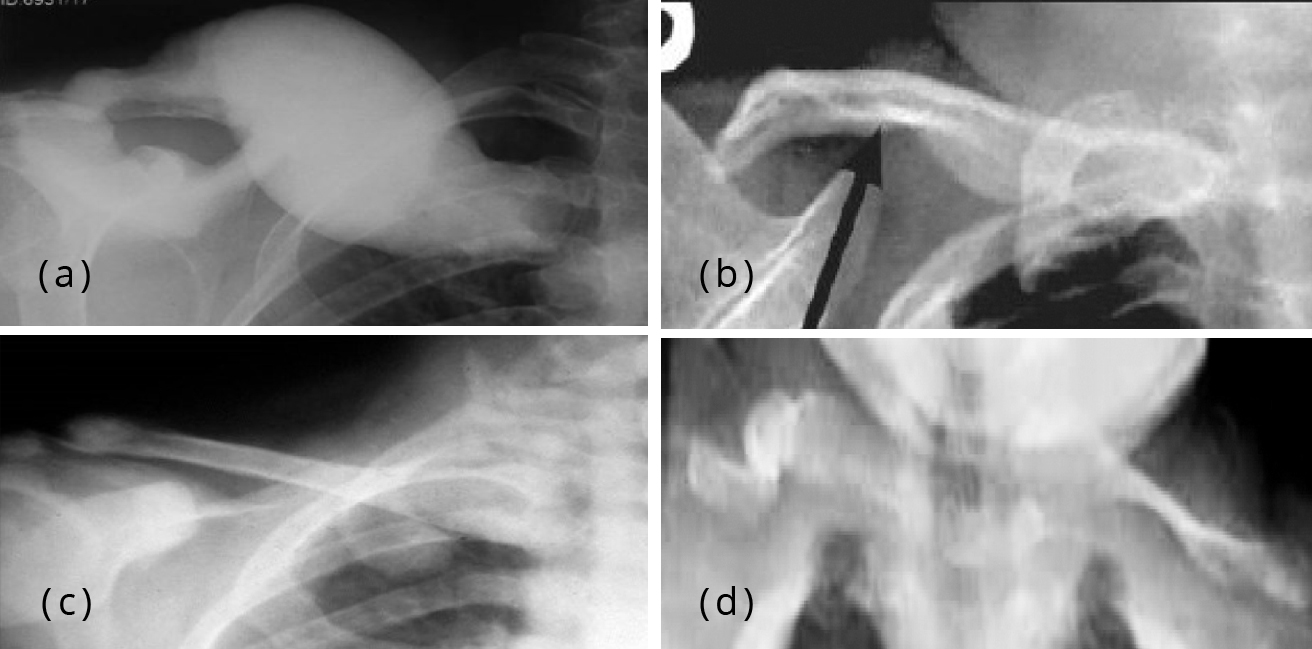

Radiographic images of a 10yearold male with Pyle disease. A, B Pyle S Disease A rare bone dysplasia characterized by long bones with wide and expanded metaphyses, thin cortical bone and bone fragility. Pyle disease is a rare bone disorder characterized by long bones with wide metaphyses, thin cortical bone, and bone fragility leading to fractures. Pyle disease is a disorder of the bones. Pyle's disease, also known as metaphyseal dysplasia, is a rare. Pyle S Disease.